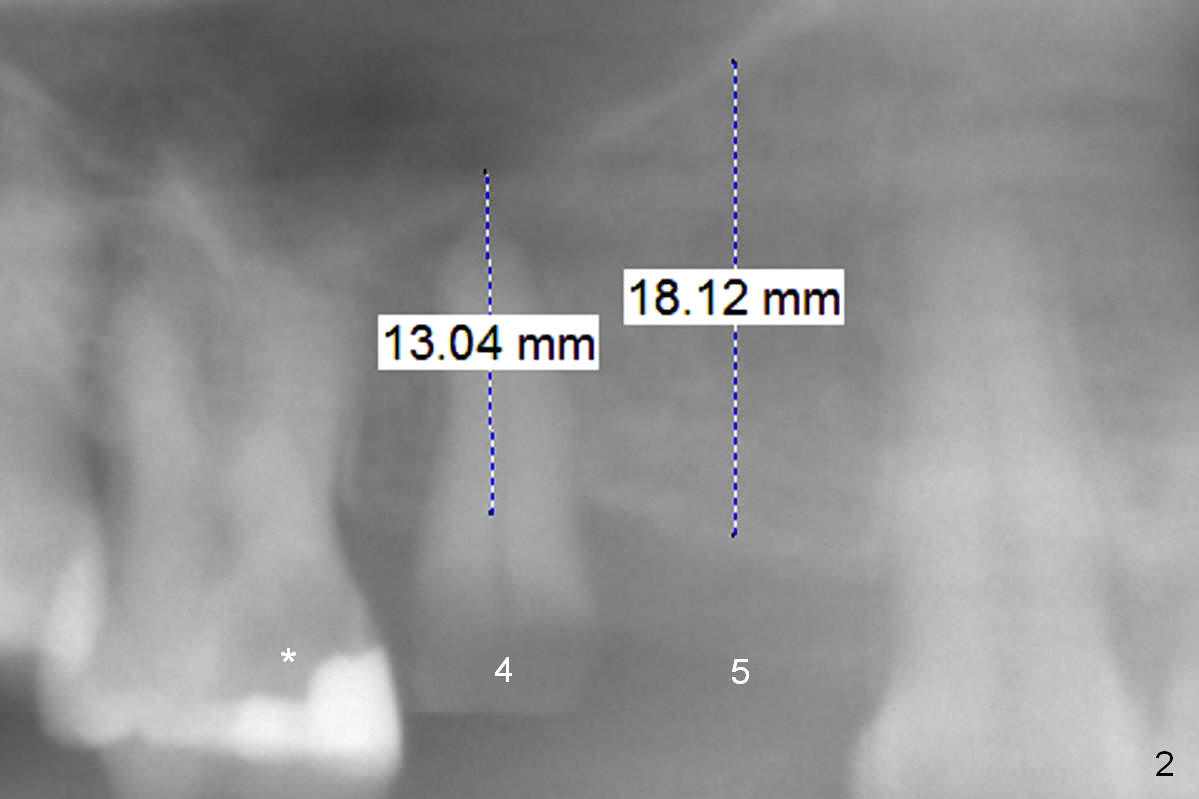

A 39-year-old woman presents to clinic with chief complaint "I cannot eat well". Multiple implants are required for functioning (Fig.1). After finishing root canal therapy at #11, work will be done in the upper right quadrant: including redoing composite at #3 after removing caries (Fig.2 *), extraction of #4 (Clindamycin) and implants at #4 and 5. The ridge at #5 is moderately atrophic. Magic split is to be used to gain access and begin bone testing and expansion, followed by Magic expanders. The latter will be used for #4 site development. Long implants will be placed to obtain maximal stability for immediate provisional. The latter will abort if occlusion is found to collapse severely. Take impression and bite registration if necessary for implantation at the lower right quadrant.